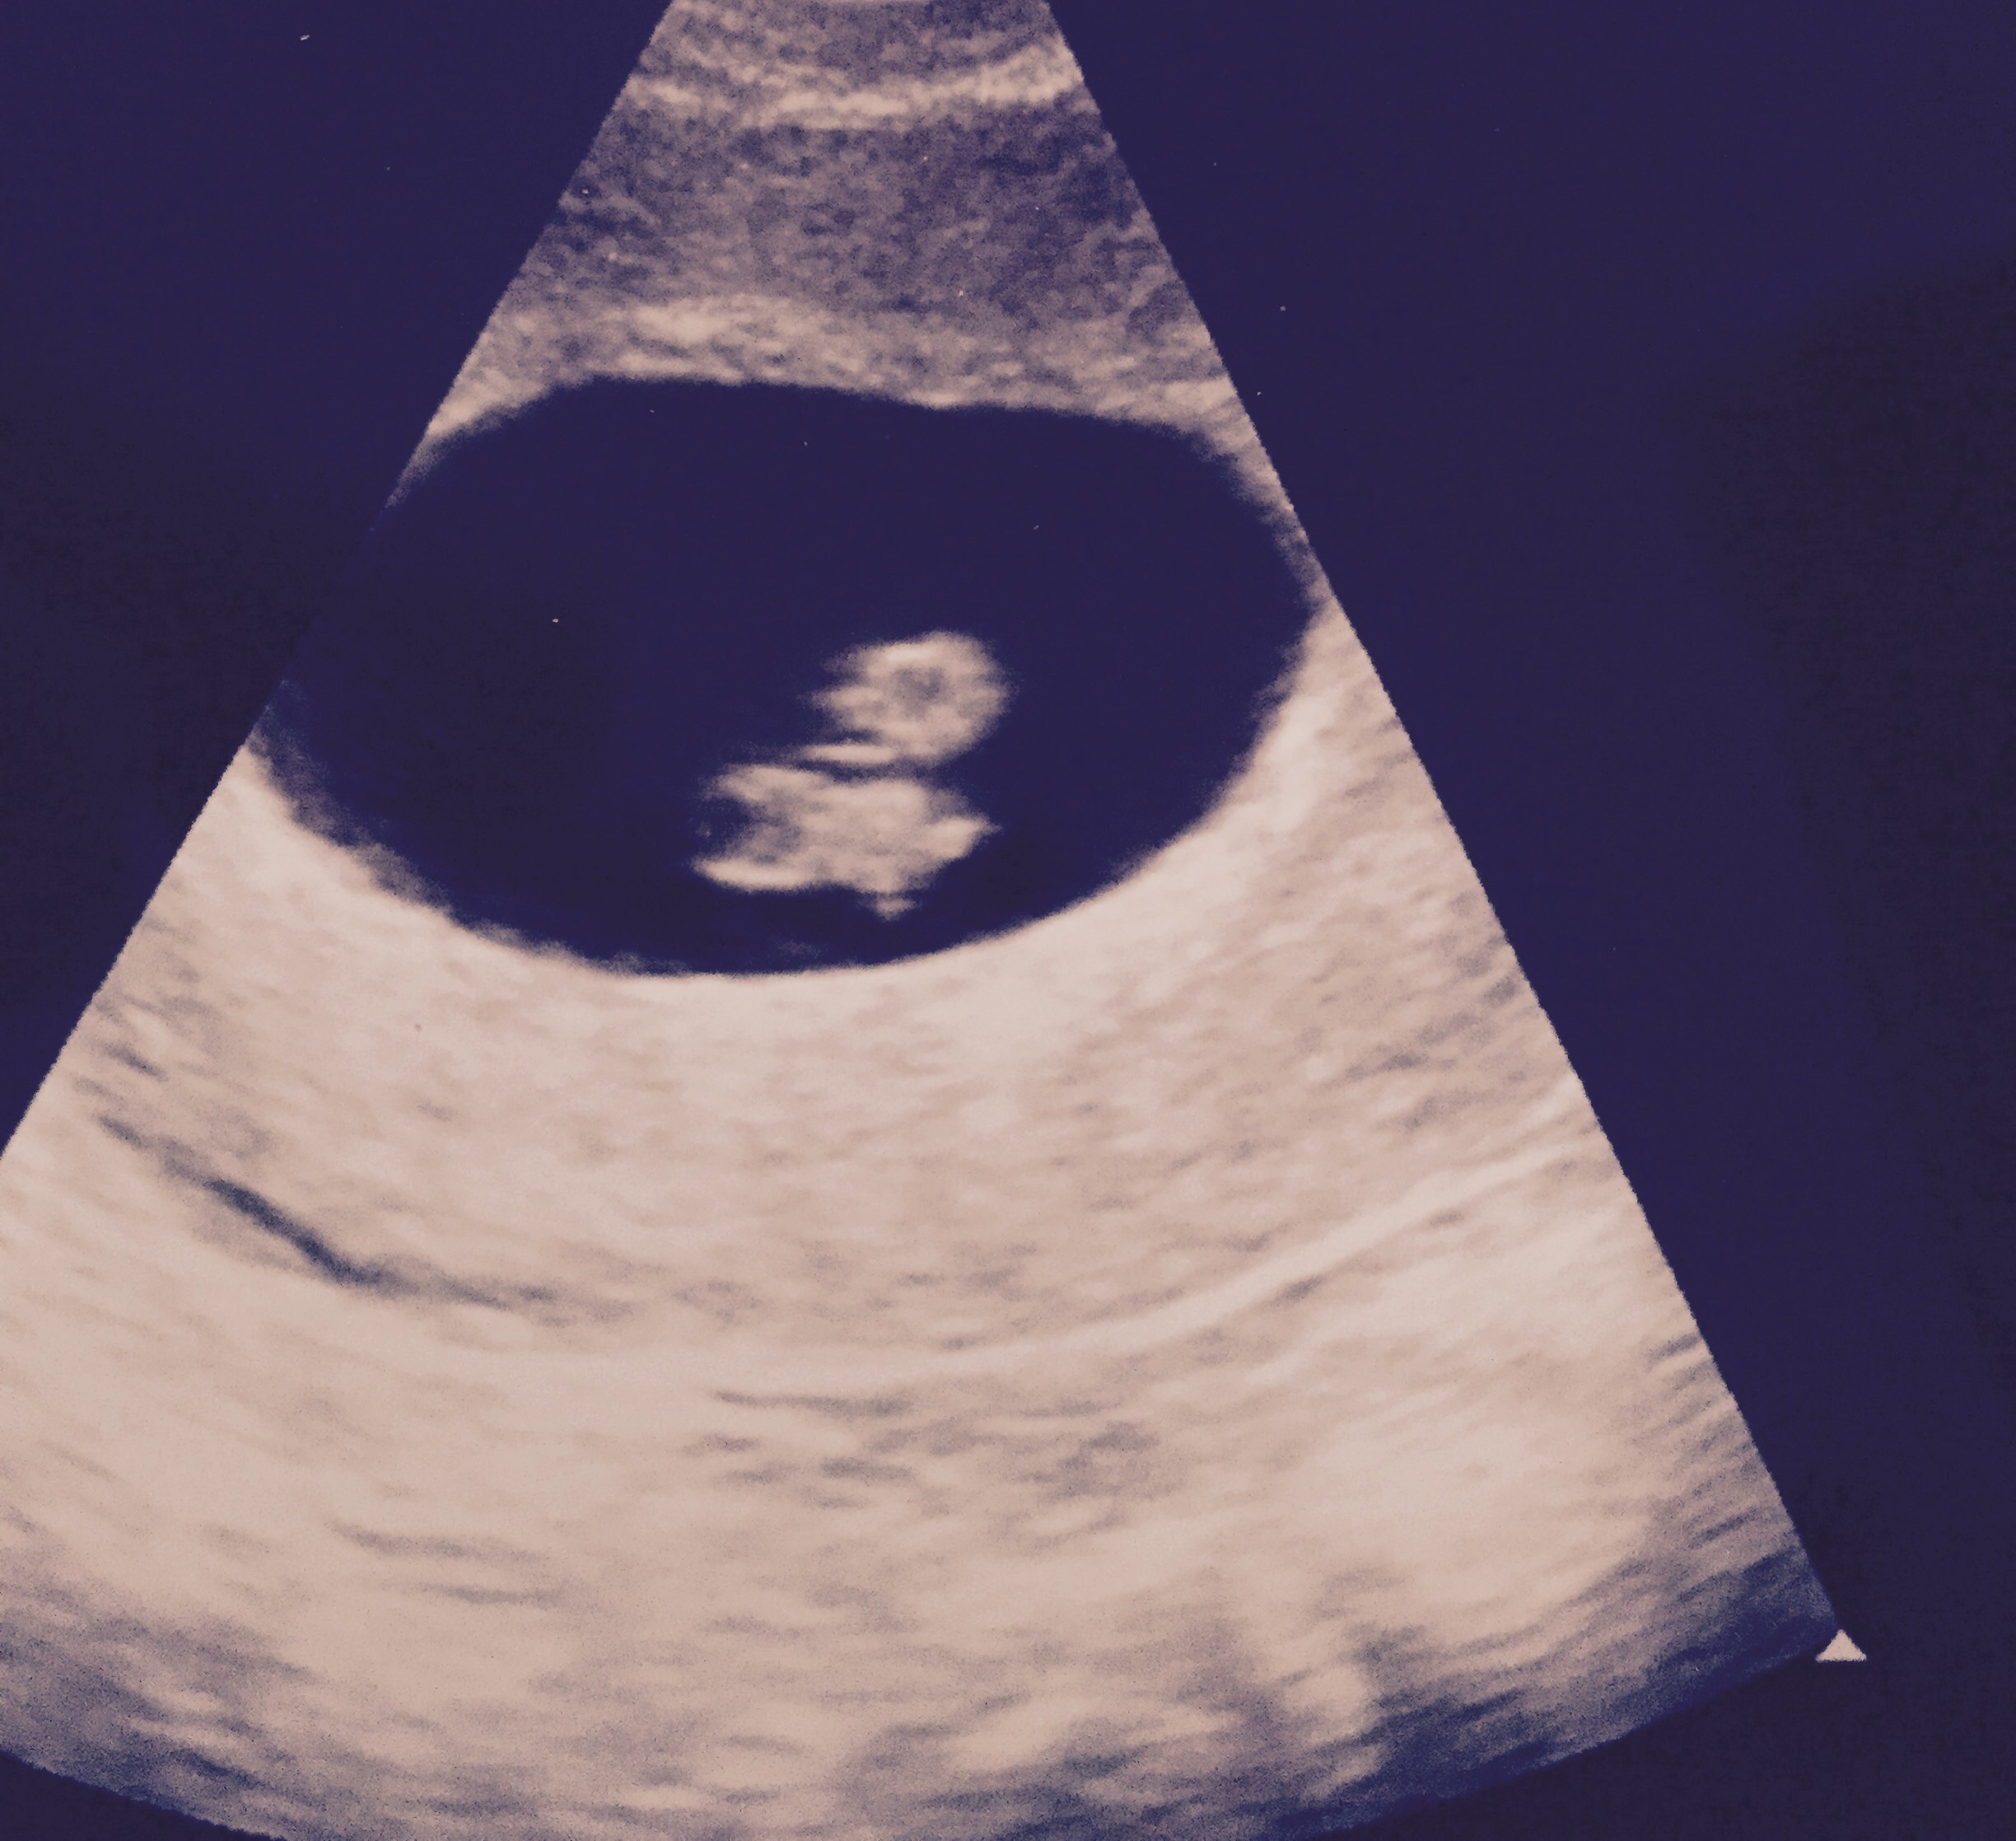

Absolutely the most surreal moment of mine and my husband's life! Our baby's first picture!! Yesterday at 8w1d ... by far the most exciting thing we've ever seen!! Our little raspberry/peanut!!